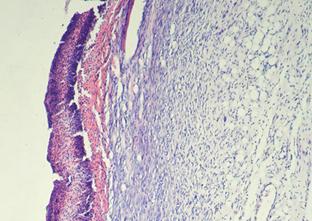

Таким образом, преобладание в грануляционной ткани фибробластов у животных опытной группы обеспечивает более быстрый темп созревания соединительной ткани, чем в контроле, на 3Ц4 дня, с закрытием раневого дефекта эпителием к 19-м суткам (рис. 16), тогда как, у животных контрольных групп раны находились под струпом до 19-х суток исследования. У животных КГ-1 ни в одном случае эпителий полностью не закрывал поверхность инфицированного повреждения кожи.

Рис. 16. Крыса. 19-е сутки после инфицирования дефекта А - ОГ; Б - КГ-1; В - КГ-2; 1 - некротизированная ткань (струп) на поверхности раны; 2 - созревающая соединительная ткань; 3 - сформированная соединительная ткань; 4 - эпителий, закрытие раны; Окраска гематоксилином и эозином; А, Б, В, Г (Об. 4х.; Ок. 10х).